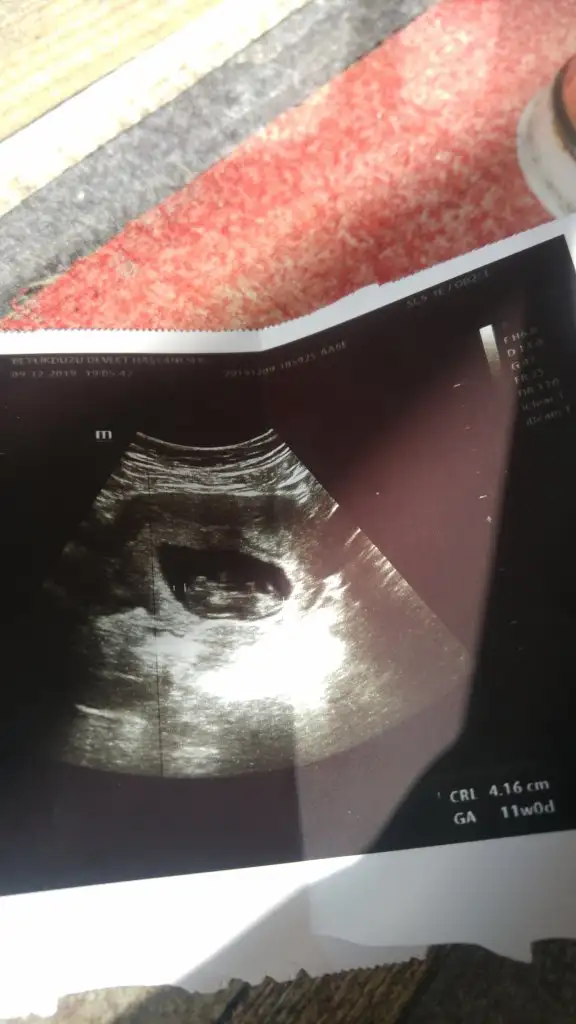

Bende gittiğimde 12 haftalıkti ultrasonda 12+4 çıkmıştı nasıl geçmiş dedi anlamadım.11 ile 14 haftalarda yapılıyor hala yaptirabilirsin. Geçmiş olsun tabi önce diğer hastalığını önlem almalısın.Bende bugün bebegimi kalp atışını sesli duydum haftasını yakalamış 11 haftalık olmuş herşeyi güzel 2 li teste geç kalmışım özelde yptir olmazsa 16 18. Hafta da 3 lu 4 lu test var dedi sadece benim sanırım idrar yolu enfeksiyonum var tahlilerde lokosit yassı epitel çıkmış çarşamba görecek doktorum

Bu da benim minnosum